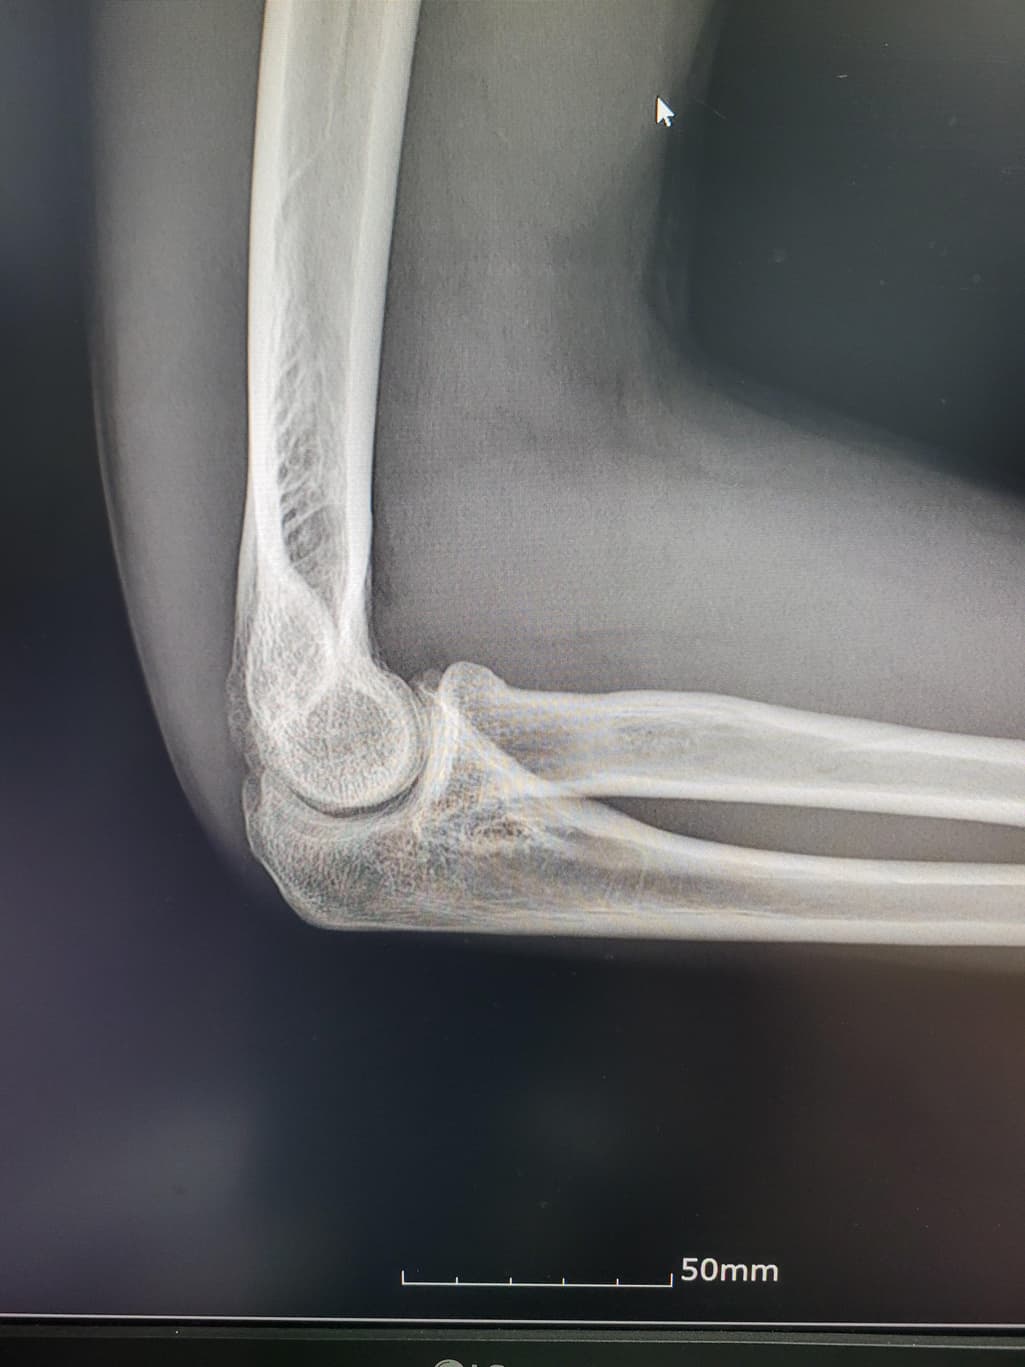

이거 활액막연골종인지좀 봐주세요(x-ray 첨부)

팔이 아파서 여러병원 찾아다니느라 엑스레이 사진도 복사해왔는데 1,2년 전에 비해서 팔꿈치에 동그란 게 생겼더라구여 이게 뭔지 모르겠습니다

과거에 활액막연골종으로 같은 부위를 수술받은 적이 있습니다

첫 번째 두 번째 사진이 가장 최근입니다

활액막연골종은 일반적으로 엑스레이에서 뼈의 경계가 부풀어 오르거나 변형된 모습이 나타날 수 있습니다.

엑스레이에서 종양은 종종 비정상적인 경계와 불규칙한 모양을 보입니다 뼈의 구조와 혼합된 모습 일 수 있습니다.